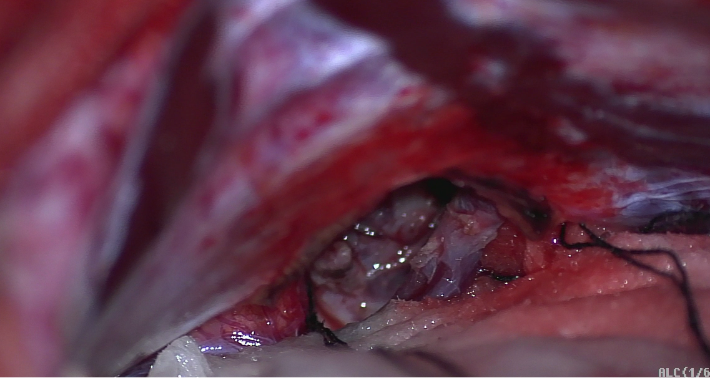

解剖蛛网膜后暴露松果体区域肿瘤病变。

切除松果体区病变后显示三脑室后部区域及重要静脉保护情况。